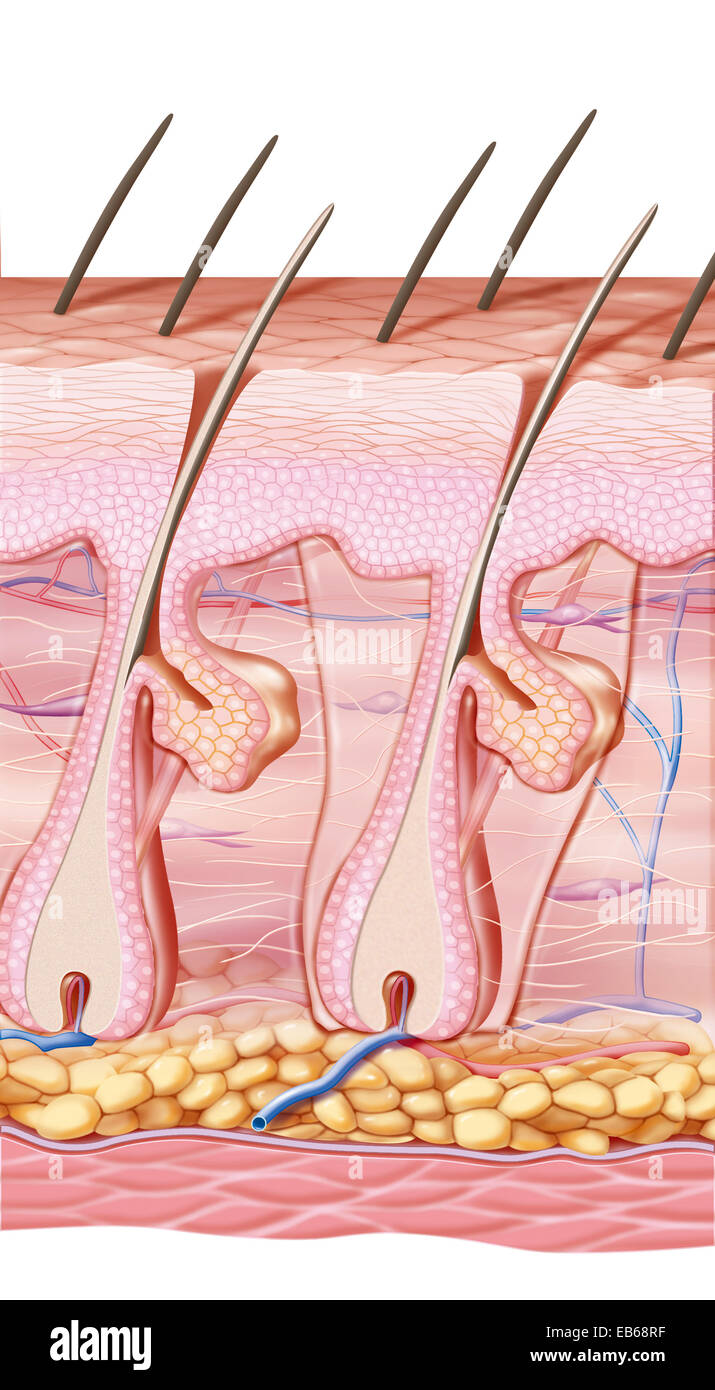

SCAR DRAWING Stock Photohttps://www.alamy.com/image-license-details/?v=1https://www.alamy.com/stock-photo-scar-drawing-75741327.html

SCAR DRAWING Stock Photohttps://www.alamy.com/image-license-details/?v=1https://www.alamy.com/stock-photo-scar-drawing-75741327.htmlRMEB68RB–SCAR DRAWING